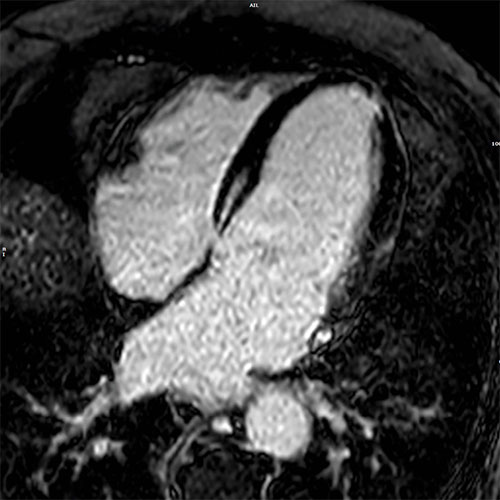

Cardiac MR images of a patient with non-ischemic cardiomyopathy showing delayed enhancement and severe mitral regurgitation.

PSIR - 4 chamber view